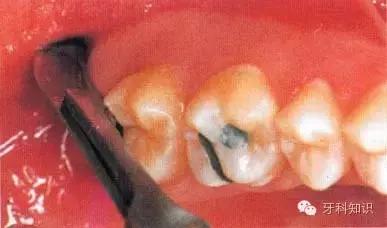

4.断根拔除出:首先要了解每个牙的牙根数目和分布情况。拔除断根时应根据不同情况采取不同方法。如断根边缘露于牙槽骨之间,将牙根挺出。断根位于牙槽窝内或部位很深者,则用骨凿凿除一部分根周骨壁,形成缝隙,然后插入根挺或根尖挺,将断根挺出(图5-12)多根牙折断牙根尚聚在一起者,可用骨凿将联结处劈,分成几个单根,然后分别取出(图5-13、5-14),上述方法仍难拔出的断根,可切开并翻起颊侧粘骨膜瓣,凿除部分颊侧骨质,暴露牙根,然后取出断根,缝合粘骨膜瓣及牙龈。

图5-12 断根拔除法示意图